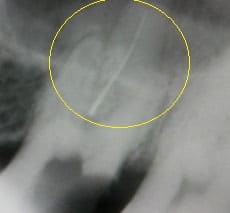

このケースは、他医院で抜髄根管治療を行っていた方です。8回通院したが、痛みが全く取れないとの事で来院しました。根管内には根管を掃除するリーマーが破折し、折れ込んでいました。リーマー除去、根管清掃、殺菌消毒をし、1回で痛みも消失しました。